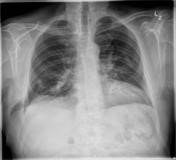

Şəkil

Kliniki müayinə zamanı döş qəfəsi divarında yumşaq konsistensiyalı, tənəffüs aktı zamanı ölçüsünü dəyişən, ağrısız şişkinlik müəyyən olunur. Rentgenoloji müayinə zamanı diaqnozu təsdiqləmək olur. Şübhəli hallarda KT müayinəsi çox faydalıdır, defektin ölçüsünü müəyyən etməyə imkan verir.